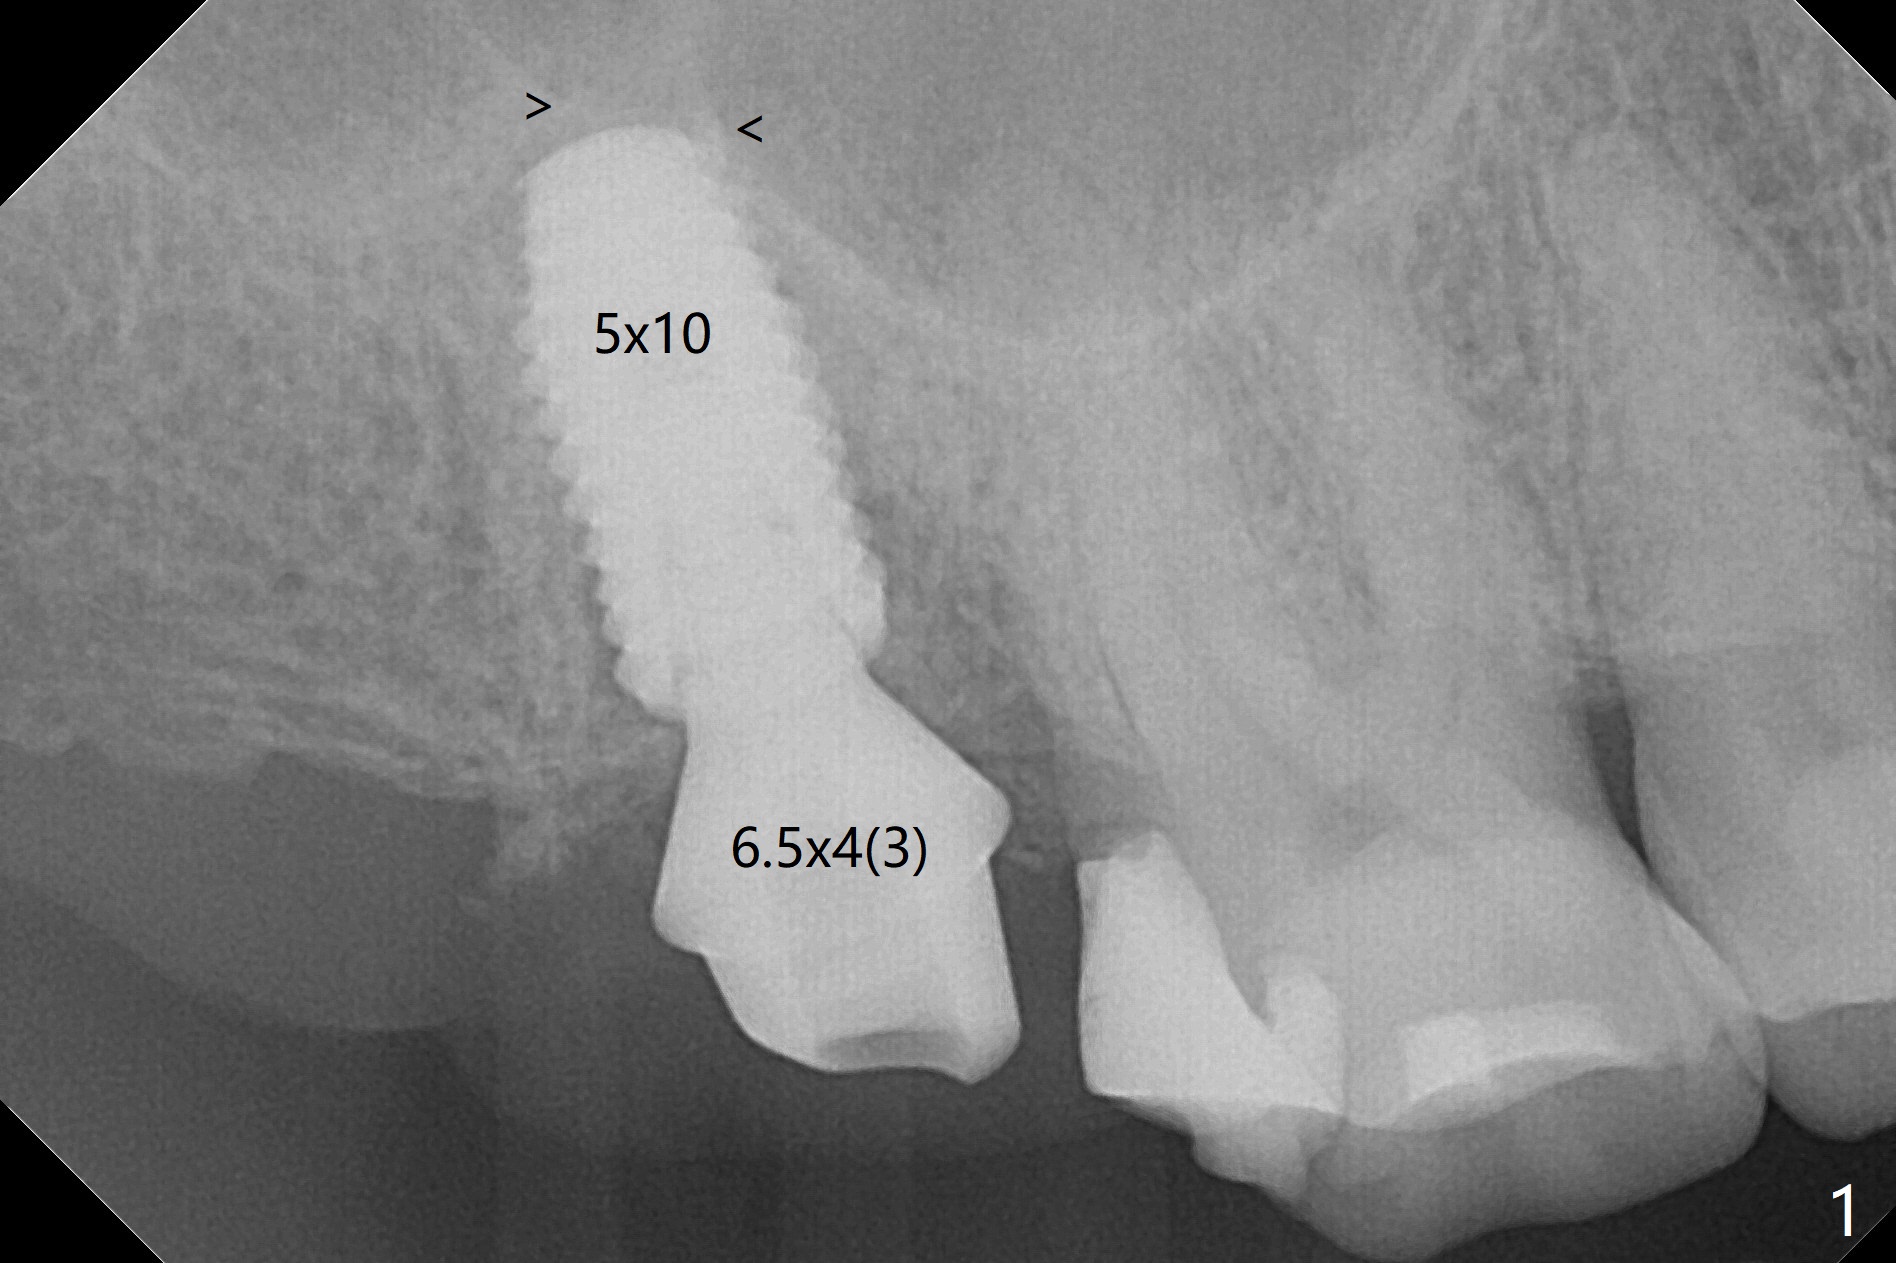

A 5x10 mm implant, placed in the buccal socket, achieves insertion torque of >55 Ncm after underprep (last drill 4 mm, as compared to 4.5 mm for normal prep). There is limited break of the sinus floor (Fig.1 arrowheads). No treatment is rendered for the mucocele. The implant heals without tenderness over the anterior sinus wall nearly 4 months postop (Fig.2). A crown is cemented 6 months postop (Fig.3 (5.2x4(4) mm abutment)); there is no gap between the abutment and implant, as compared to Fig.1,2 (6.5x4(3) mm). The implant functions without sign or symptom of bilateral sinusitis (no percussion associated with the tooth #13) 11 months post cementation (Fig.4). In fact the abutment is incompletely seated (Fig.5: <). Bone profile drill should be used to trim the mesial crest before reseating crown/abutment.